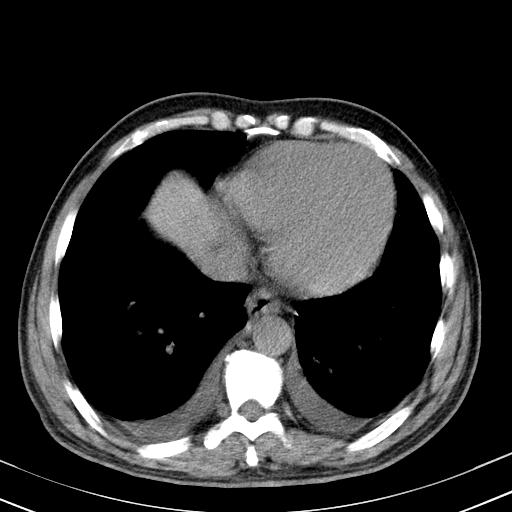

以下是引用zxl51642在2010-3-21 17:06:00的发言:[br]右下中心型肺癌并阻塞性肺炎/不张,纵膈淋巴结肿大,右侧大量胸腔积液,左侧少量胸腔积液,少量腹水。建议纤维支气管镜进一步检查。